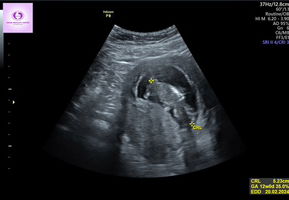

Bun usia kehamilan 18w bagusnya folamil genio apa yang folamil gold yaah